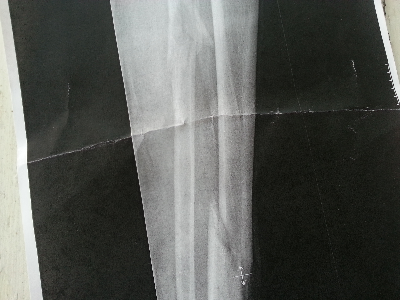

Ibland blir det inte som man tänkt sig. Det blev inte fika varken hos grannen eller pappan eller någon oktoberfest. Istället blev det ambulansfärd till Visby lasarett och akut operation av ett vänsterben som gått tvärt av och stack ut genom skinnet.

Maken skulle göra akrobatiska konster på bryggarhustaket för att byta en takpanna, tappade fotfästet och trillade 2,5 meter ner och landade på fötterna. Benen håller inte för det, men det var trots allt bättre att det var ett ben än ryggen eller nacken. Ta en sekund idag och tänk på hur fort saker kan förändras. I morgon kanske inte alls är en annan dag ...

Ambulansen kom från Hemse, det gick fort och ambulanskillarna var fantastiska. Jag åkte efter med bilen, och när jag kom in var ortopeden på plats och maken fick bästa möjliga vård på en gång. Alla var proffsiga och trevliga, vi fick komma till röntgen direkt och operation så fort clementinen inmundigad som mellis i väntan på lunch hade passerat systemet.